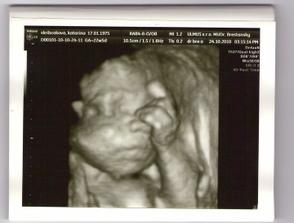

3D - nas poklad

Nas drobcek na 3D

krasne :o) ktory tyzden to bol?

bolo to teraz v nedelu 24.10 a bola som 22 tyzden 5 den.Ale mala je o tyzden popredu tak podla merania lekara bola 23 tyzden 5 den